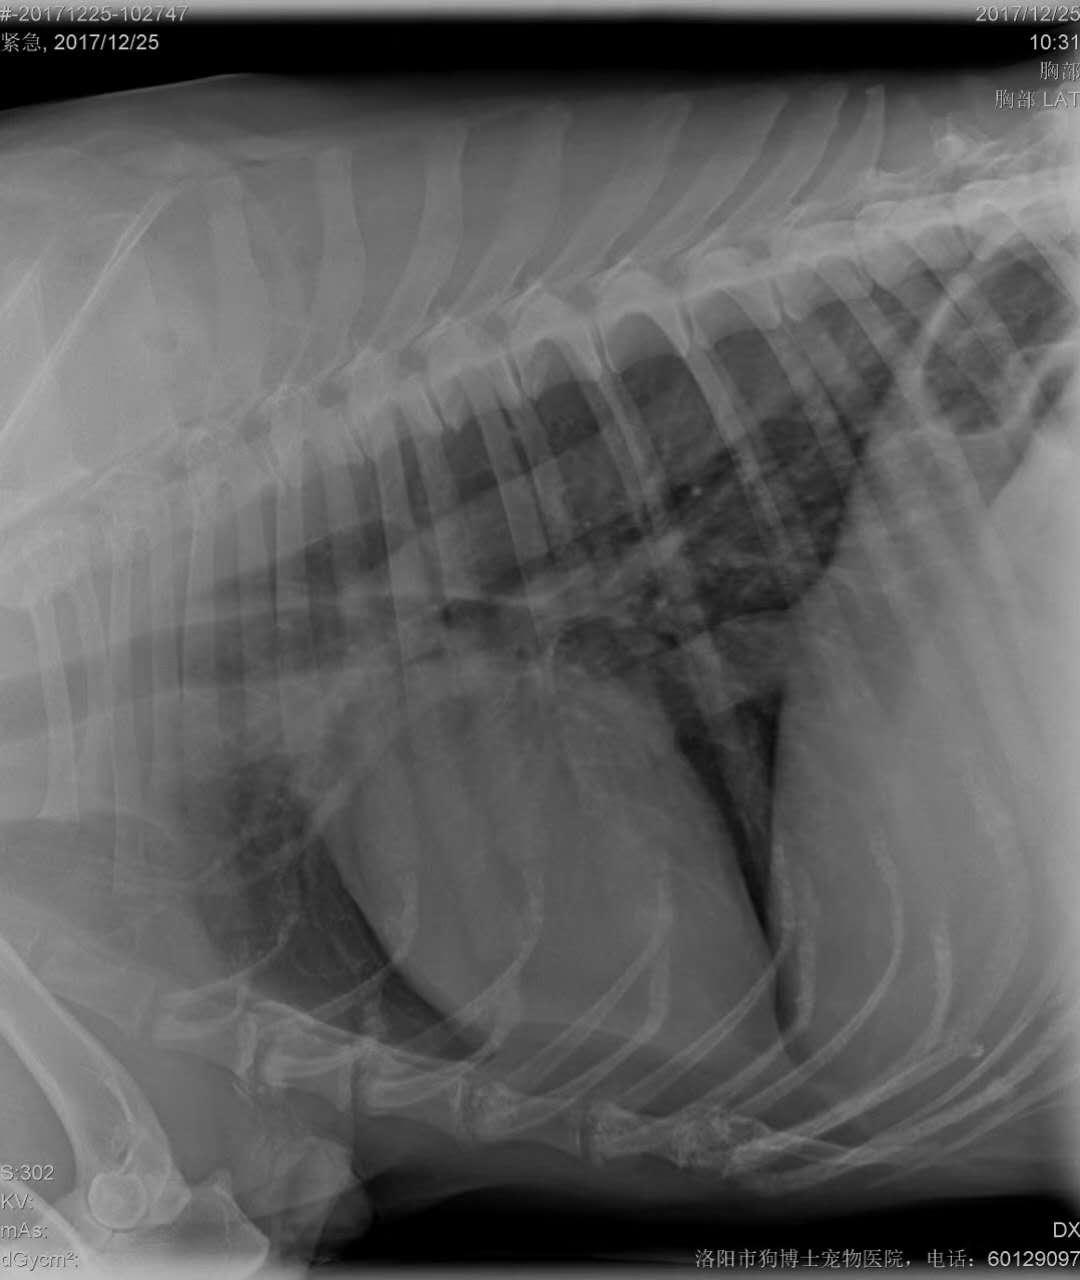

右前肢肘部腫瘤摘除:德牧,巴圖,10歲,來自孟津,系老客戶*,右前肢肘部腫瘤病程已久,*近有增大趨勢,遂來醫(yī)院手術摘除。PS:寵主們如果發(fā)現(xiàn)您的愛寵身上有不明腫塊,建議盡快帶醫(yī)院處理,不敢拖延,否則部分腫瘤有轉移風險,如果發(fā)生轉移,預后不良。